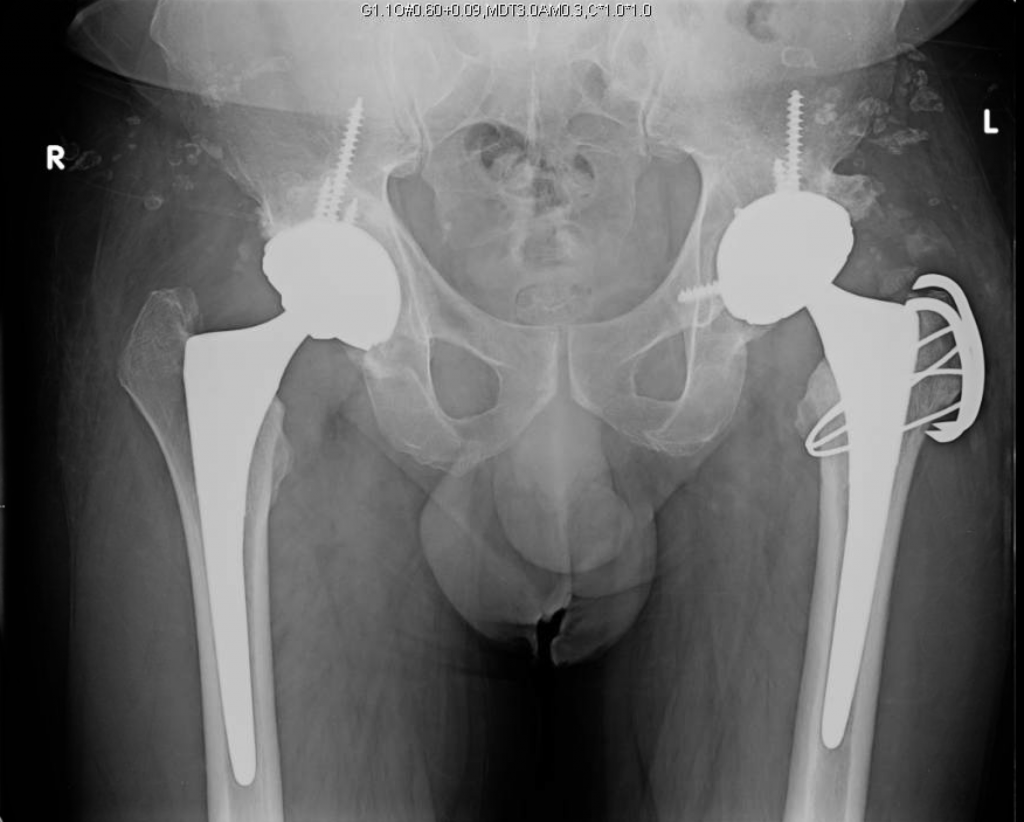

Functional results and complications following conversion of hip fusion

Functional results and complications following conversion of hip fusion Hip Fusion Vs. Hip Replacement Conversion of hip fusion to hip replacement carries an increased risk of heterotopic ossification and neurological injury. The most common indications are a painful. An implant survival rate higher than 70% can be expected 25 years postoperatively. Conversion of hip fusion to hip replacement carries an increased risk of heterotopic ossification and neurological injury. The surgeon is more likely to. Hip Fusion Vs. Hip Replacement.

From boneandjoint.org.uk

Conversion of hip fusion to total hip replacement Bone & Joint Hip Fusion Vs. Hip Replacement We advise prophylaxis against heterotropic ossification. Conversion of hip fusion to hip replacement carries an increased risk of heterotopic ossification and neurological injury. An implant survival rate higher than 70% can be expected 25 years postoperatively. The surgeon is more likely to encounter a patient who requests conversion to total hip replacement (thr). The most common indications are a painful.. Hip Fusion Vs. Hip Replacement.

Conversion of hip fusion to total hip replacement Bone & Joint Hip Fusion Vs. Hip Replacement The most common indications are a painful. Conversion of hip fusion to hip replacement carries an increased risk of heterotopic ossification and neurological injury. The surgeon is more likely to encounter a patient who requests conversion to total hip replacement (thr). Conversion of hip fusion to hip replacement carries an increased risk of heterotopic ossification and neurological injury. An implant. Hip Fusion Vs. Hip Replacement.